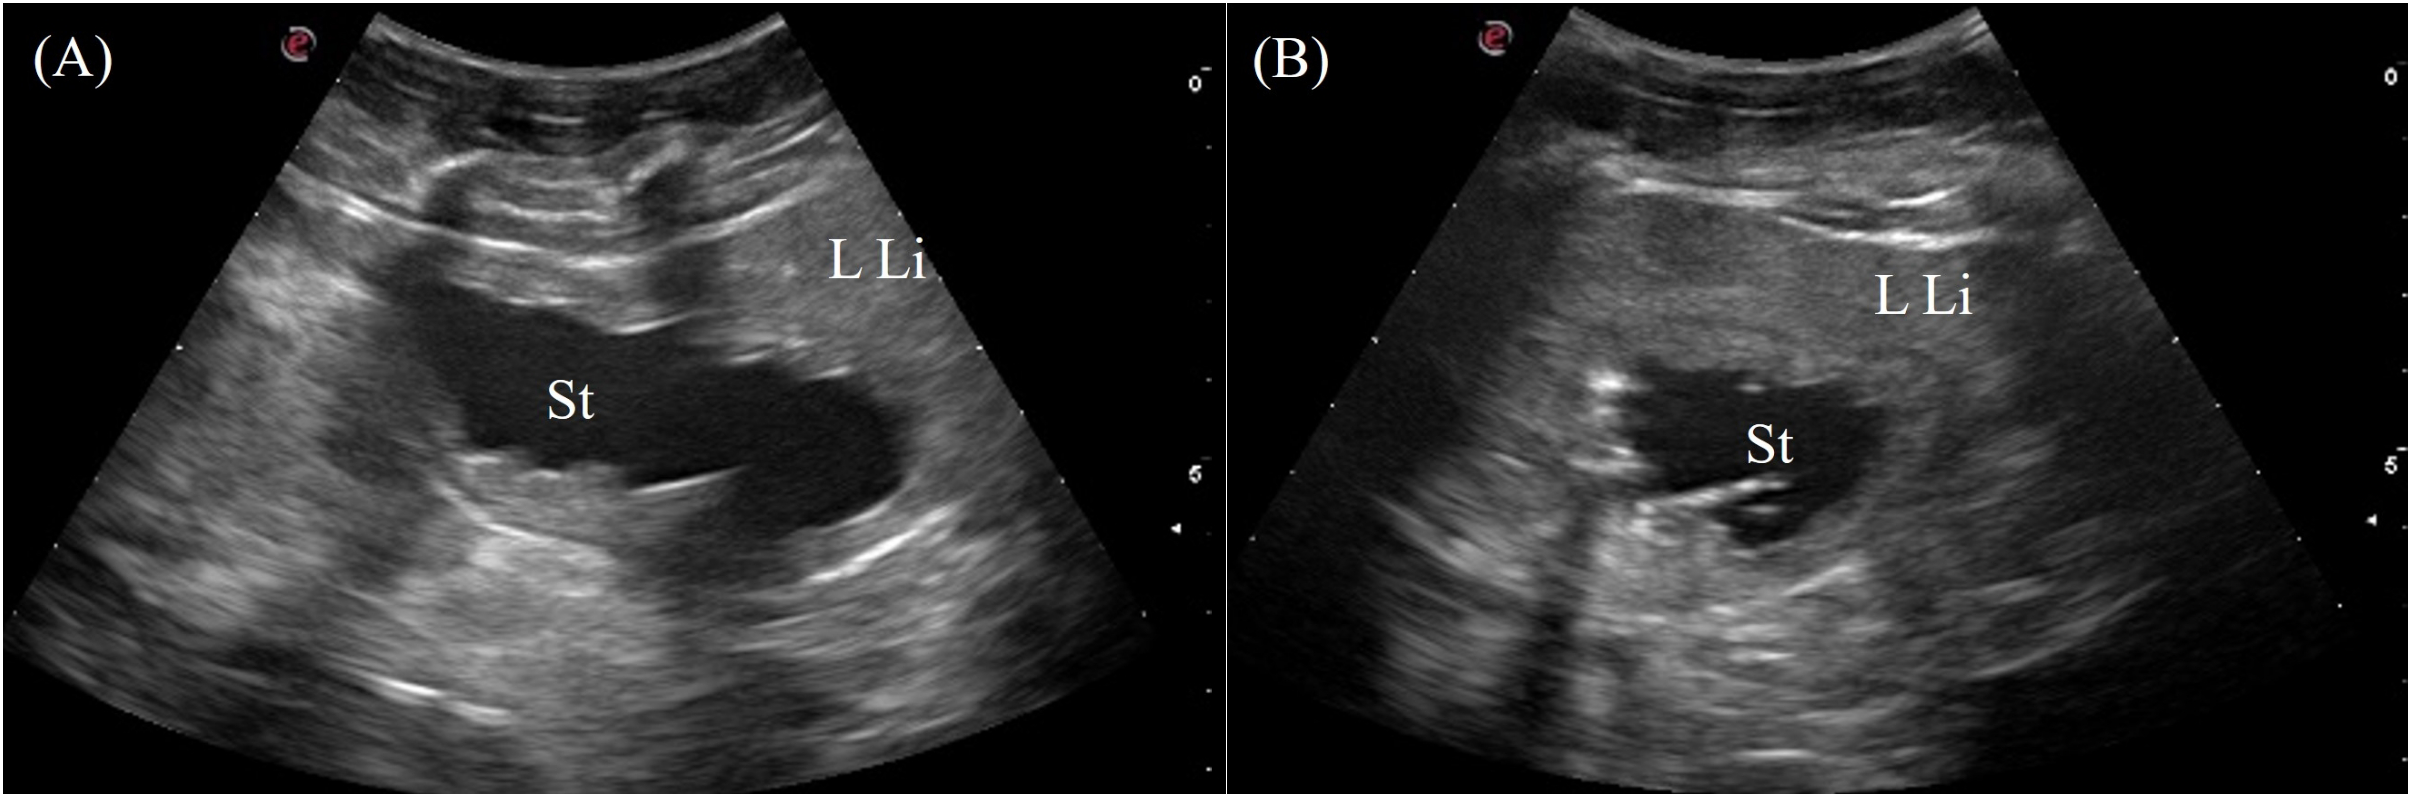

3.3.6 Gastrointestinal tract and pancreas

The stomach was immediately adjacent to the left coelomic wall caudal to the left liver lobe. The gastric fundus was visualized in 7/7 animals from the left lateral view intercostally and just caudal to the last rib (Figure 3, transducer position 2). The entire gastric fundic wall could be visualized with the transducer when filled with anechoic fluid. Small amounts of hypoechoic to hyperechoic foci or material were also detected depending on the type of ingesta of the animal. The gastric fundus had homogenous, thick, convoluted folds isoechoic to the hepatic parenchyma and a thin hypoechoic outer muscular layer (Figure 10). Gastric motility was occasionally observed. The pars pylorica was difficult to visualize and evaluate as it was a small segment between the gastric fundus and duodenum that often collapsed without ingesta.

Figure 10

Ultrasonographic appearance of the gastric fundus in (A) sagittal and (B) transverse views from the left lateral approach in Alligator sinensis. [LLi, left liver lobe; St, stomach].